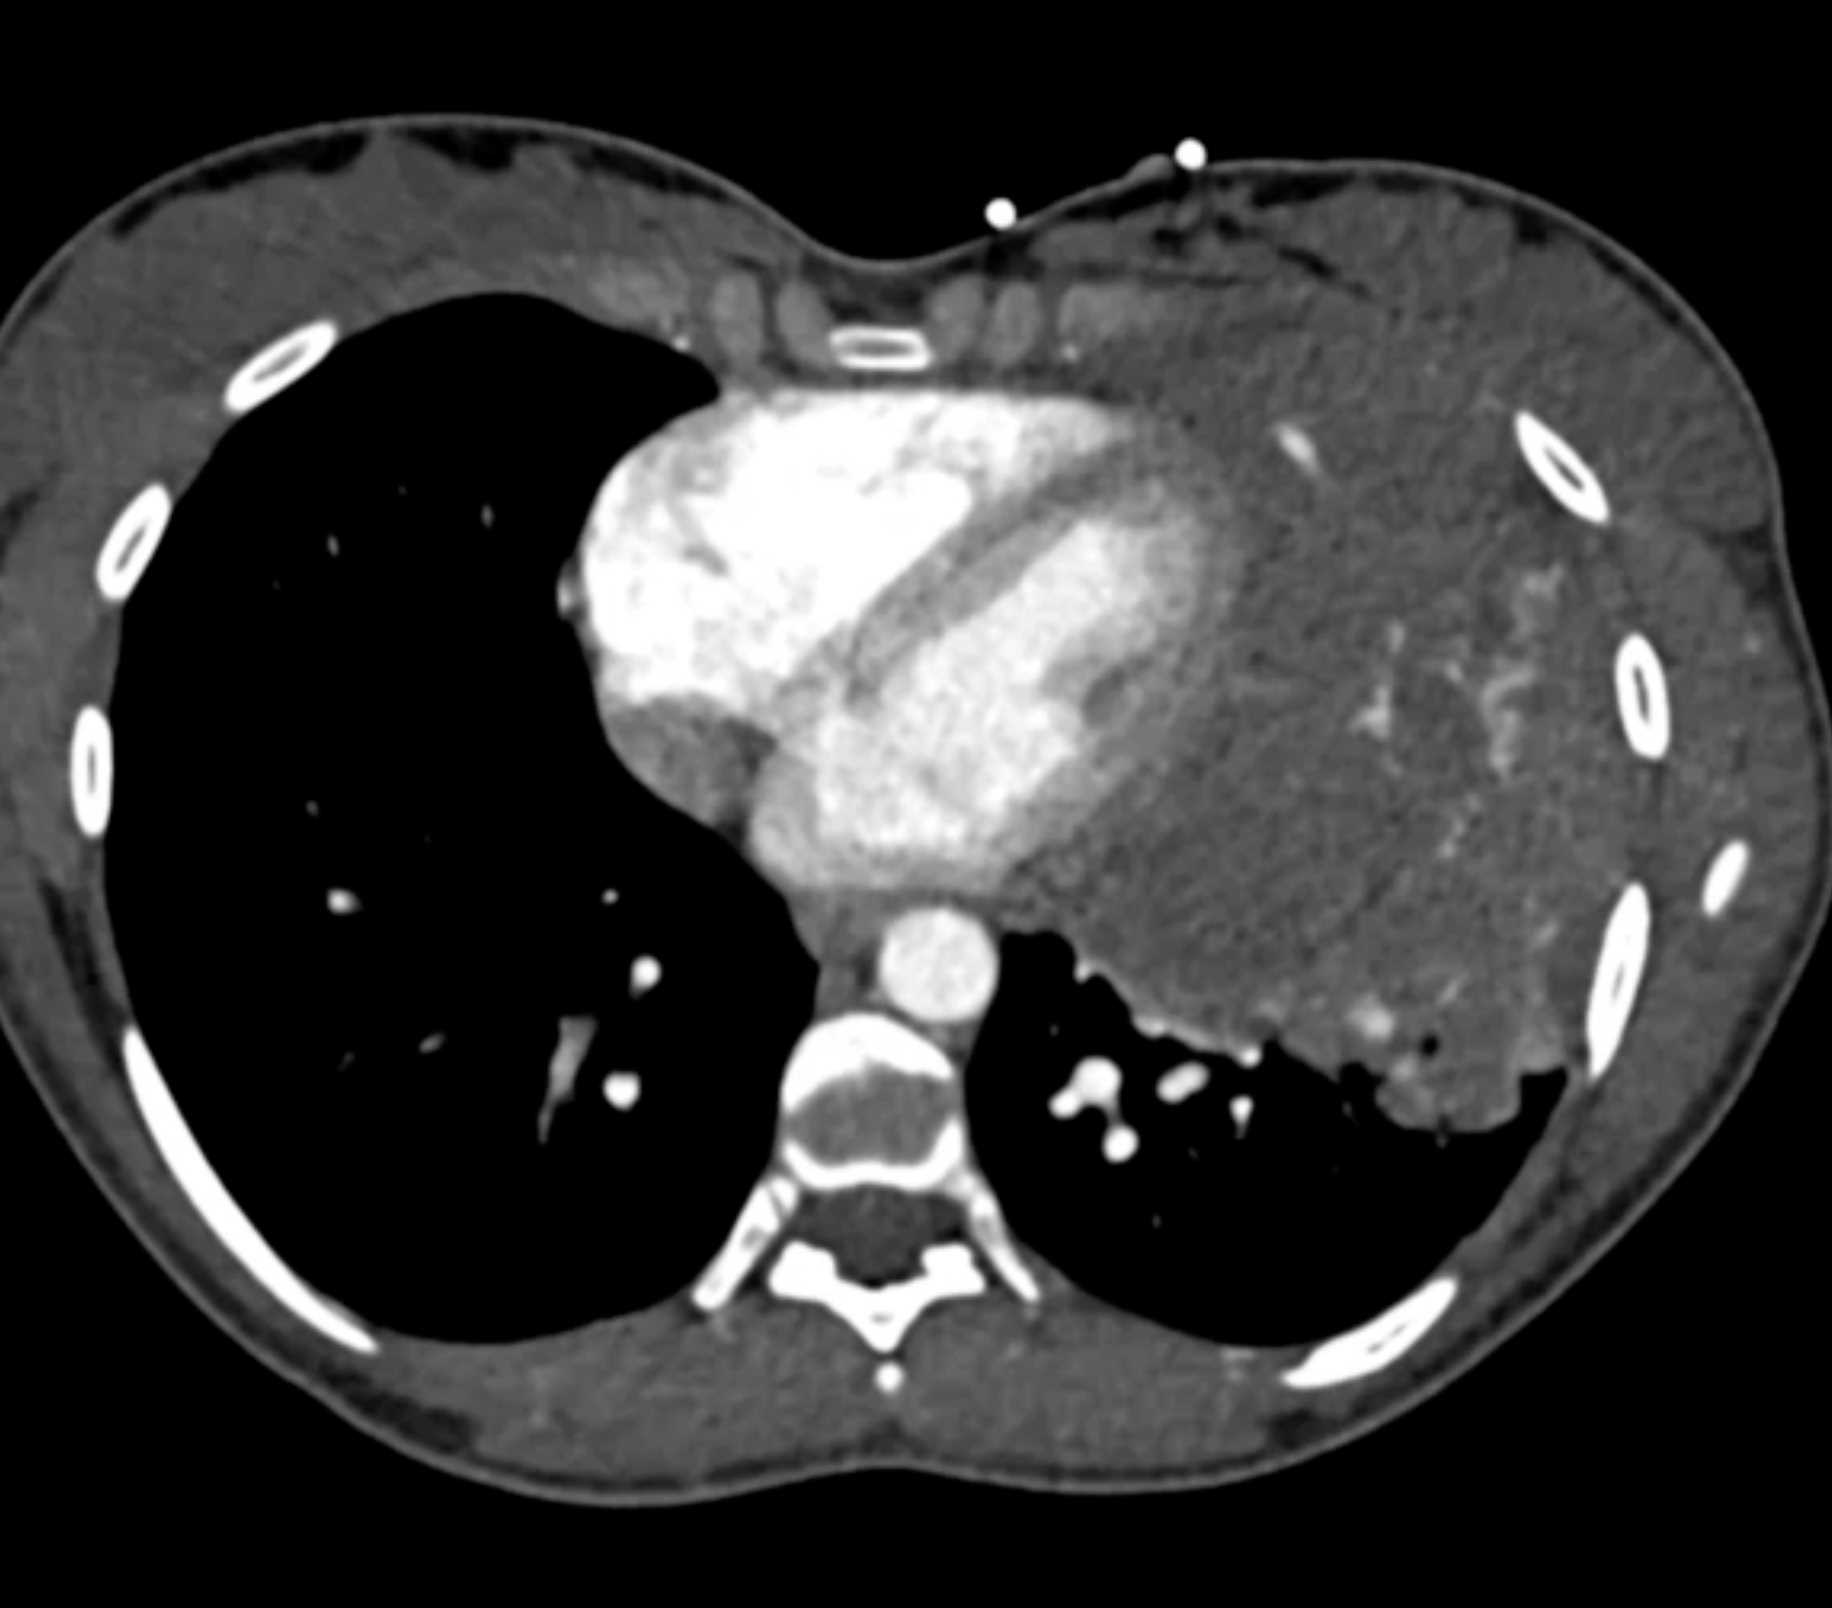

Subtle Adenocarcinoma Pancreas